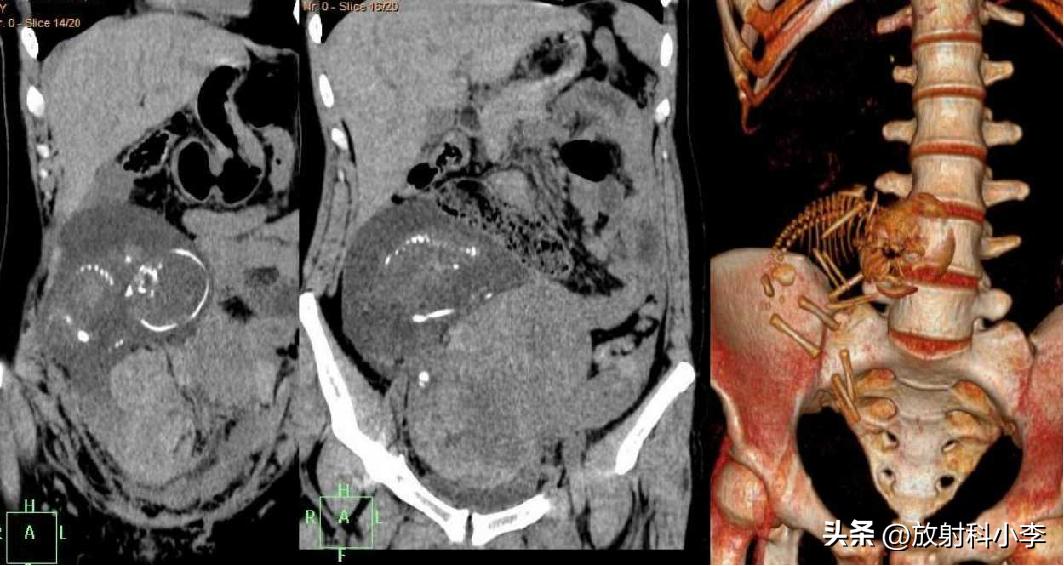

F,27Y

增强CT示子宫前无强化实性肿块,而双侧卵巢正常;失状位示子宫前壁附着蒂扭曲。